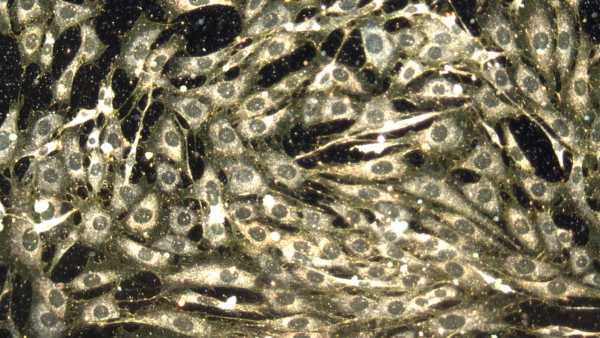

Але нове дослідження, яке порівнювало імунні системи людей похилого віку та молодшого віку, не виявило послідовного збільшення біологічних маркерів запалення з віком. Натомість, старіння, здається, перепрограмує Т-клітини — важливі імунні клітини, які допомагають навчати тип лейкоцитів, які називаються В-клітинами, виробляти антитіла у відповідь на віруси та вакцини.

Дослідники виявили суттєві відмінності в Т-клітинах пам'яті — імунних клітинах, які «пам'ятають» минулі інфекції та допомагають організму швидше реагувати наступного разу, коли з'являється патоген.

У людей похилого віку зростаюча кількість Т-клітин пам'яті переходить у стан, який змінює їхню реакцію на загрози — змінюючи їхню взаємодію з В-клітинами. Дослідження показало, що коли Т-клітини пам'яті не працюють належним чином, В-клітини стають менш ефективними у виробленні антитіл у відповідь на інфекції або вакцини. Тим часом Т-клітини пам'яті молодих людей вміло реагували швидко та посилювали очікувану антитільну відповідь.

Ці імунні зміни, здається, відбуваються незалежно від запалення та інфекцій латентними вірусами, які залишаються в організмі після первинного зараження та можуть переходити в сплячий стан, не викликаючи жодних явних симптомів. Інфекції цими вірусами, такими як цитомегаловірус (ЦМВ), часто звинувачують у ослабленні імунної системи з віком. Однак дослідження показало, що люди віком до 65 років, які перенесли ЦМВ-інфекцію в певний момент свого життя, не мали ознак швидшого старіння імунітету або підвищеного рівня запальних білків.